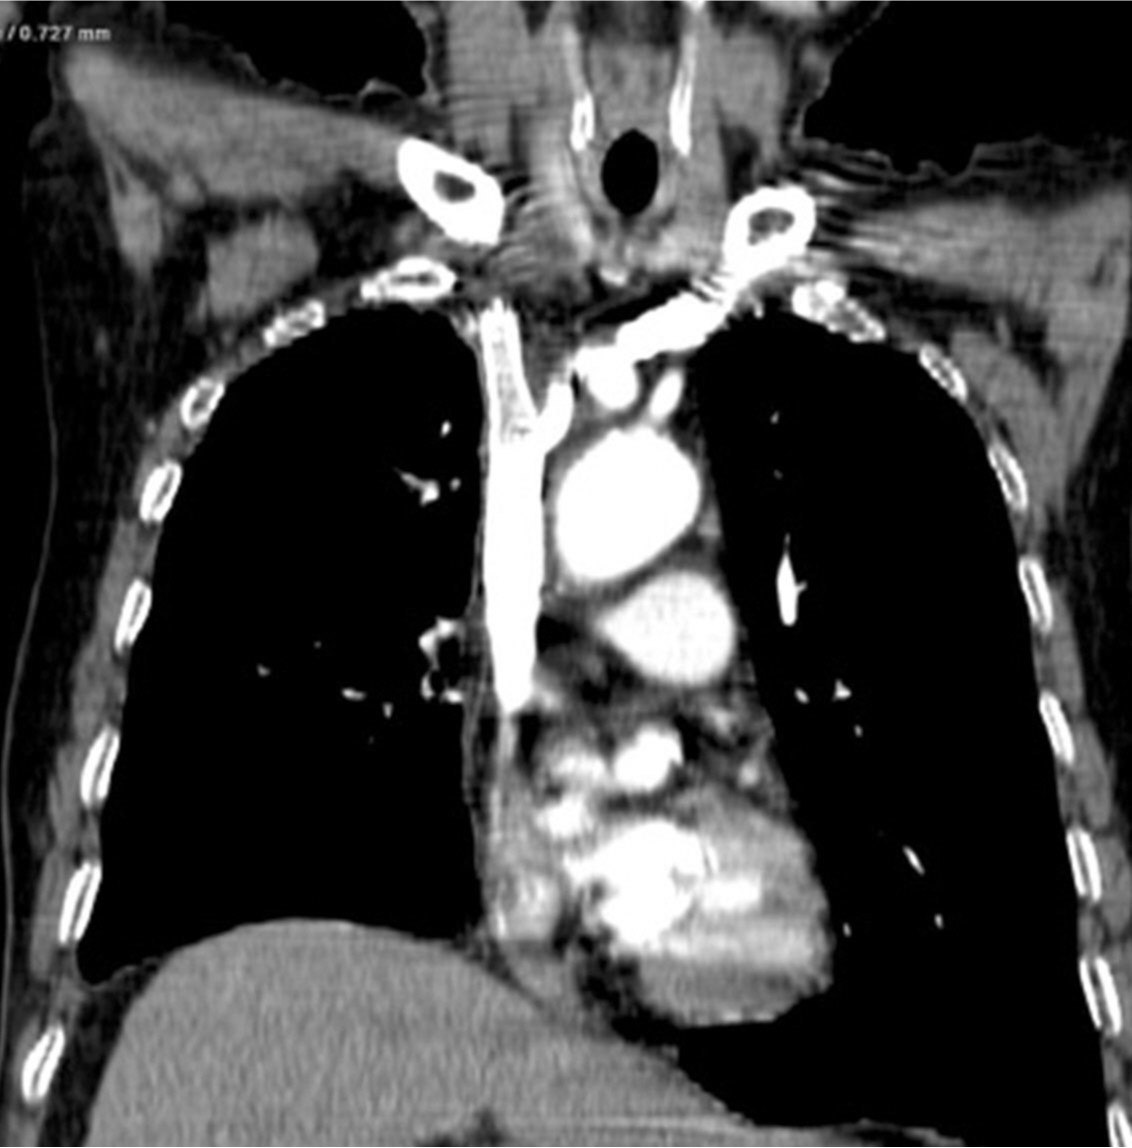

흉부 CT영상에서 폐암의 종격동 침범과 임파절 전이로 인해 상대정맥이 눌려 심하게 좁아져 있다(Fig. 1).

Fig. 1A, 1B. The axial (A) and coronal (B) images of chest CT scans show segmental severe narrowing(arrows) of the superior vena cava resulting from compression by the surrounding malignant tumor with mediastinal lymph node metastasis.